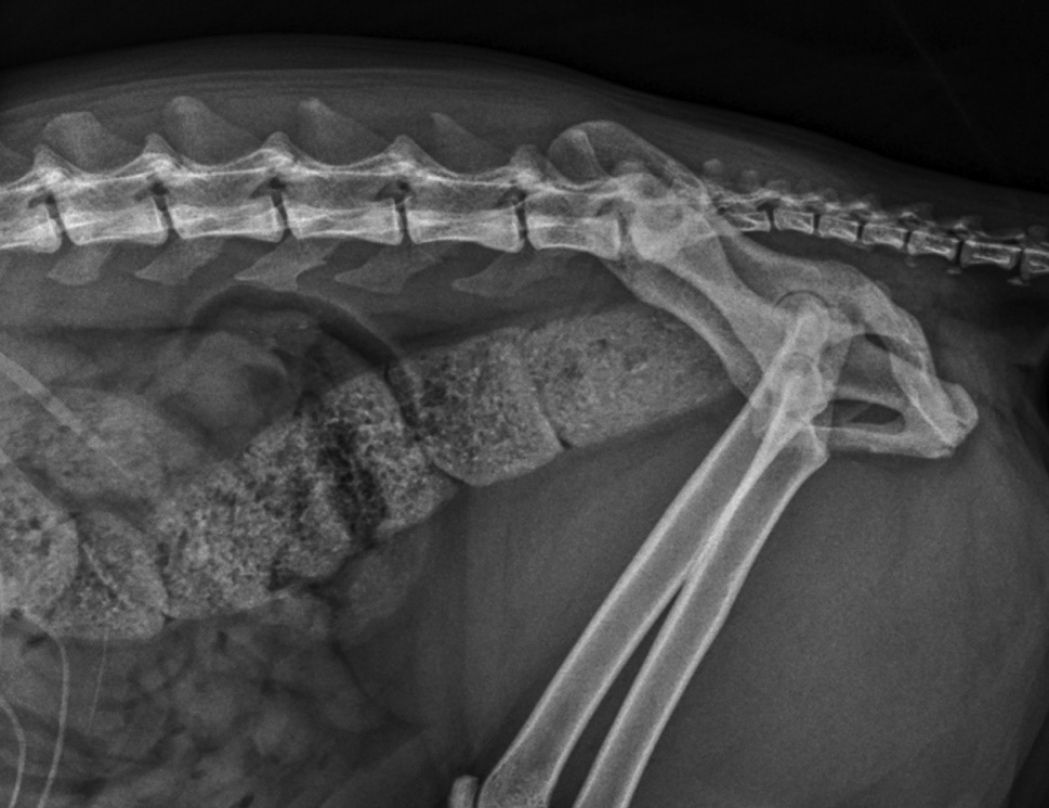

At almost five years of age, the client reported worsening of the signs, with the cat straining frequently to defecate, but only small volumes of faeces being passed. Abdominal palpation revealed large volumes of firm faeces in the descending colon and rectum. An enema was scheduled under general anaesthesia and when digital palpation revealed a stenotic pelvic canal, plain radiographs were acquired.

Radiography of the abdomen (Figure 1) revealed a full and severely distended colon. The seventh lumbar vertebra measured 17mm and the colon at its widest part measured 30mm, confirming megacolon. Views of the pelvis (Figure 2) revealed deformities consistent with malunion of the right ischium caudal to the acetabulum and of the pubis on the right side. The sacral index measured 71%, suggesting a low risk of constipation.